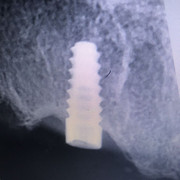

Дмитрий Л. Опубликовано 22 мая, 2019 Поделиться Опубликовано 22 мая, 2019 Коллеги, подскажите пожалуйста, чем биогоризонт запротезировать? 10 лет назад кто-то ставил. Трансфер от миса подошел, но как-то неидеально. Внутренний 6гранник, желтый, 3,5. Ссылка на комментарий

Дмитрий Л. Опубликовано 23 мая, 2019 Поделиться Опубликовано 23 мая, 2019 Я правильно определил, что это биогоризонт 3.5? Ссылка на комментарий

dentikl Опубликовано 23 мая, 2019 Поделиться Опубликовано 23 мая, 2019 3,8. у 3,5-фиолетовое 1 Ссылка на комментарий

Борис80 Опубликовано 12 июня, 2019 Поделиться Опубликовано 12 июня, 2019 (изменено) Я правильно определил, что это биогоризонт 3.5? всё верно, стандартная платформа от Израиля, который с биогора и срисован изначально Изменено 12 июня, 2019 пользователем Борис80 1 Ссылка на комментарий